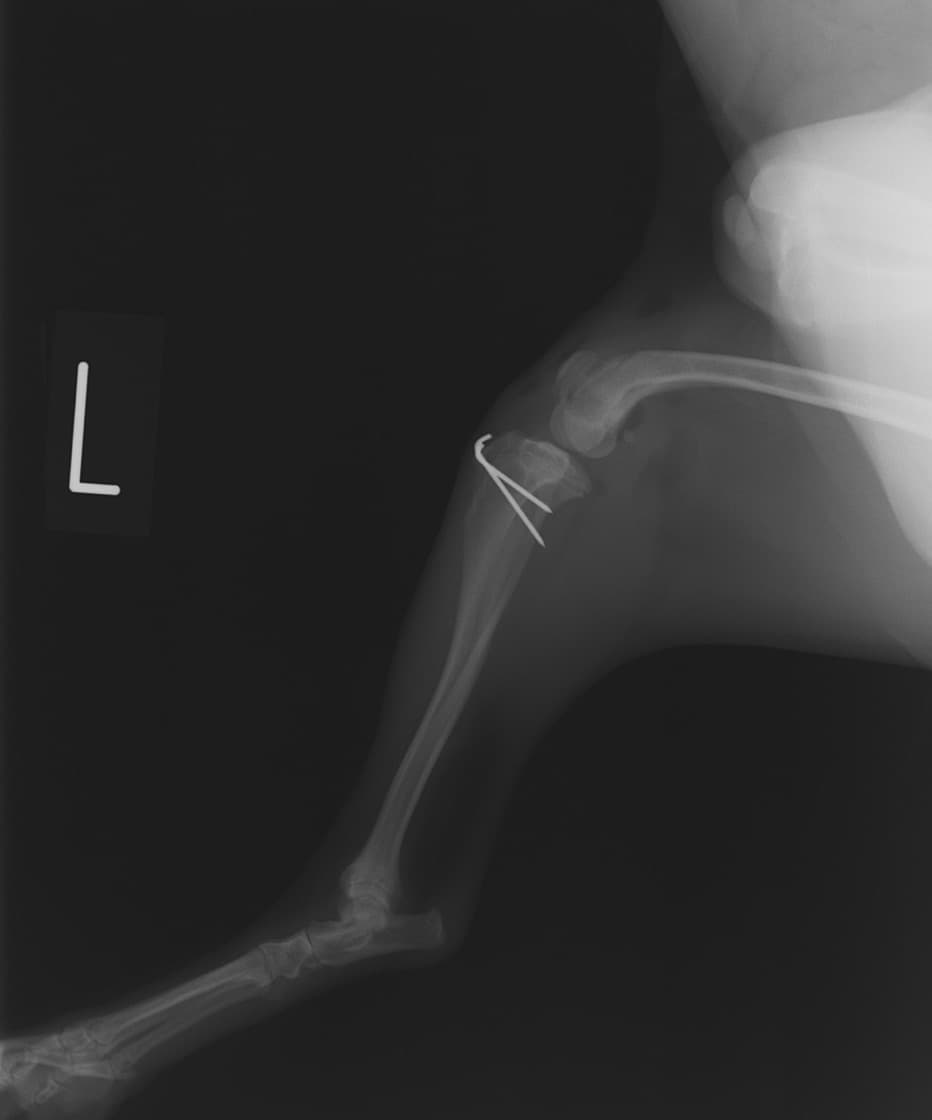

■ 症例20 ポメラニアン 8ヶ月 1.8kg

左右膝蓋骨脱臼 グレードⅢ

2ヶ月前から間欠的跛行が認められ、両膝の膝蓋骨脱臼整復術を行った。

手技は縫工筋及び内側広筋の解放、脛骨粗面の外側転位、滑車ブロック形造溝術、内外側関節包の縫縮を選択し実施した。

右側の膝蓋骨脱臼は上記手技で整復されたものの、左側はそれのみでは膝蓋骨が浮く様子が認められた。その為、PDS縫合糸にて膝蓋靱帯を1糸のみ縫合し、靱帯の縫縮を行った。

膝蓋骨脱臼は膝関節における膝蓋骨の内外側の脱臼と定義されるが、時として単純な内外の脱臼ではなく、膝蓋骨が大きく前方に浮き上がるように脱臼する場合がある。特にトイプードルやポメラニアンといった犬種に多く認められる。

内側脱臼に加えて前方への浮き上がりを矯正する為に、従来より脛骨粗面転移により膝蓋靭帯を外方と下方に引っ張り、固定する方法を選択する。膝蓋骨の前方への浮き上がりが軽度の場合は、従来法ではなく関節包の縫縮で対応していた。しかし、一部の症例で膝蓋骨の動きが悪くなり伸展機構が円滑に機能せずロボット様歩行になるケースがあった。

その為、膝蓋靭帯自体を縫縮する方法を採用した。この方法により、膝関節の伸展機構を妨げず膝蓋骨の軽度の浮きを矯正することが可能となった。

本症例の経過は良好である